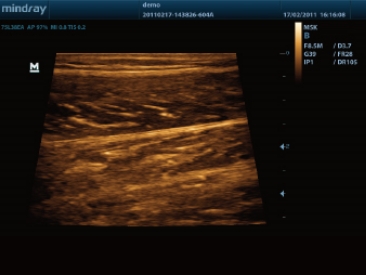

伪彩功能